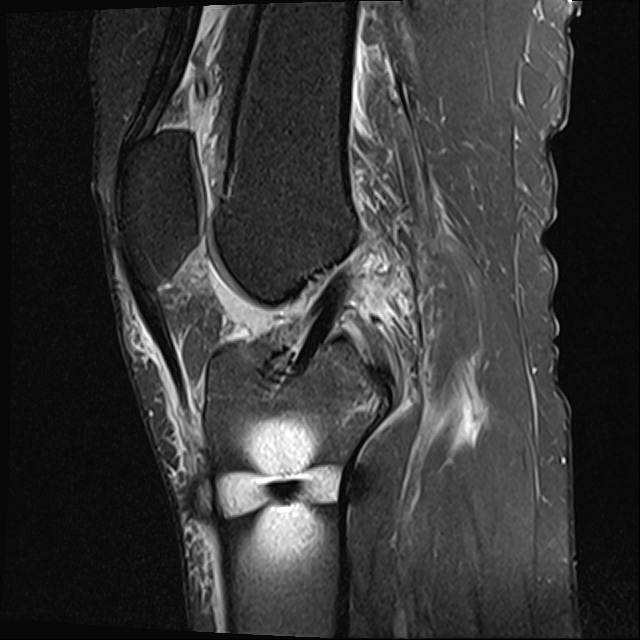

십자인대는 경골(정강이 뼈)과 대퇴골(허벅지 뼈)을 연결해주는 인대로 전방, 후방 두 개의 인대로 구성되어 있습니다. 십자인대는 무릎이 앞뒤로 흔들리지 않게 고정시켜주는 역할을 합니다.

십자인대가 파열되어 기능을 상실하고 통증을 유발하는 질환을 십자인대 파열이라고 합니다.